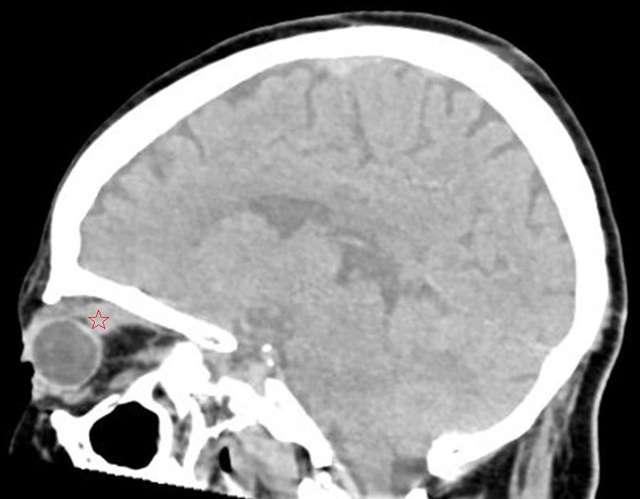

图 2 为平扫 CT,可见上直肌明显增粗(五角星)